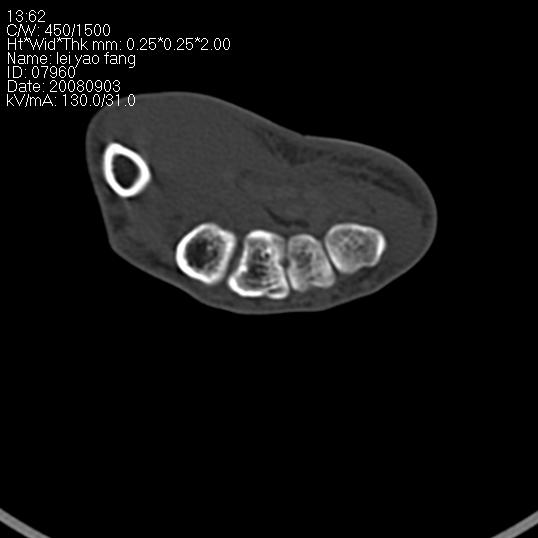

以下是引用杀毒软件在2008-9-4 17:41:00的发言:[br]考虑----舟骨囊肿